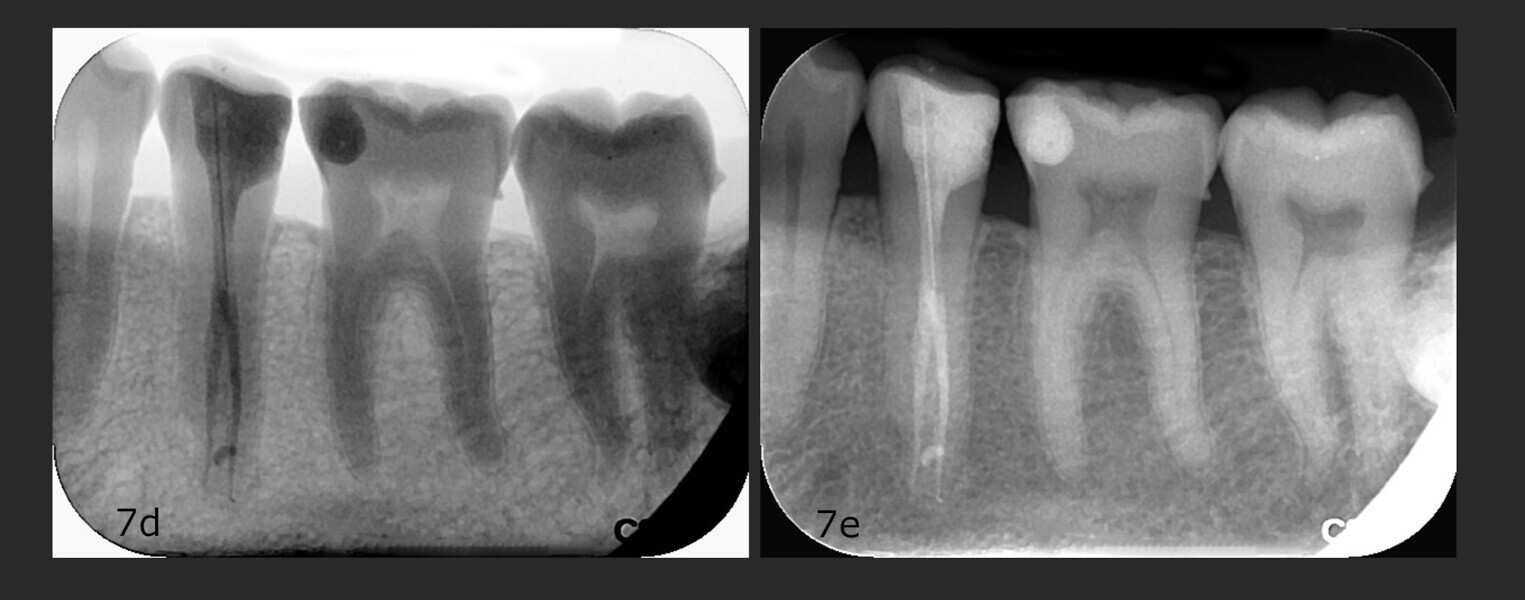

Fig. 1: Pre-op panoramic radiograph.

This was due to a special dental anatomy that had not been identified. In the middle of the root, about 13–14 mm from the cusps, the root canal split into two different canals (Vertucci Type V or deep split). This was easy to see on the initial panoramic radiograph (Fig. 1), which is why I decided to prepare the canals with HyFlex CM and HyFlex EDM files and under magnification (Figs. 2 & 3). This allowed me to follow the respective canal profiles and preserve the root canals as far as possible through optimal and centred preparation in each canal.

The follow-up appointments observed complete healing of the treated tooth (Fig. 7). Together with the patient, we decided that a crown was not necessary for the moment.